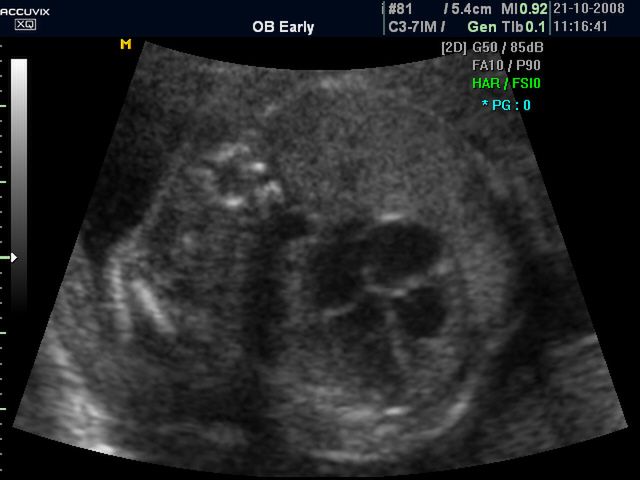

/ 10Zdjęcia płodu - 26 tydzień ciąży

Obraz

Płód w 26 tygodniu ciąży, na zdjęciu widoczne męskie narządy płciowe